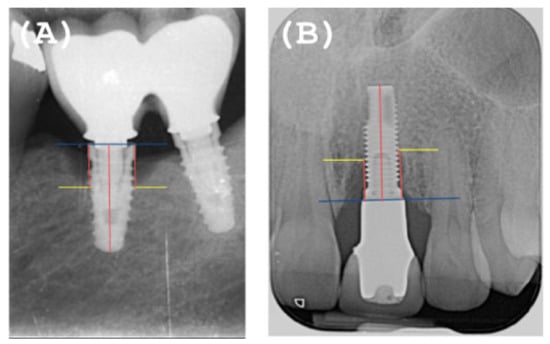

- Overcontoured or non-overcontoured prostheses: assessed by periapical radiographs and clinical evaluation by a calibrated examiner, where an overcontoured prosthesis is more associated with inflammation and the retention of bacterial plaque compared to prostheses with an adequate contour (Figure 1).

2.5. Radiographic Evaluation

- The MBL decreased from T0 to T1.

- A radiographic bone filling was obtained in most cases.